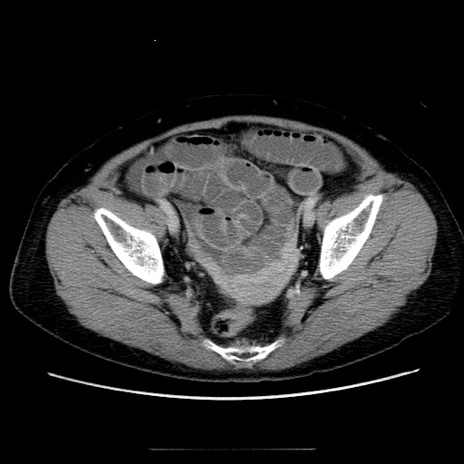

症例5(横断像)

【症例】70歳代女性

【主訴】お腹が張る

【現病歴】1週間くらい前から腹部膨満の自覚あり。昨日夜から増悪したため、本日救急外来受診。

【身体所見】意識清明、BT 36.5℃、BP 165/106mmHg、HR 80bpm、SpO2 98%、腹部:膨満、軟、自発痛・圧痛なし、触診にて不快感あり、腸蠕動音:減弱

【データ】WBC 12600、CRP 1.04